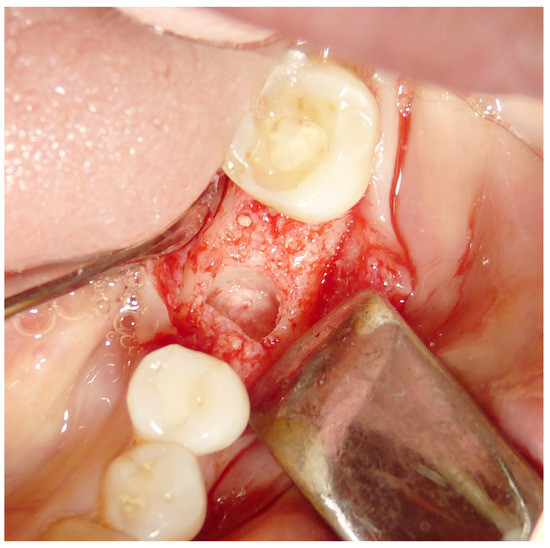

2.4. Surgical Procedures and Follow-Up